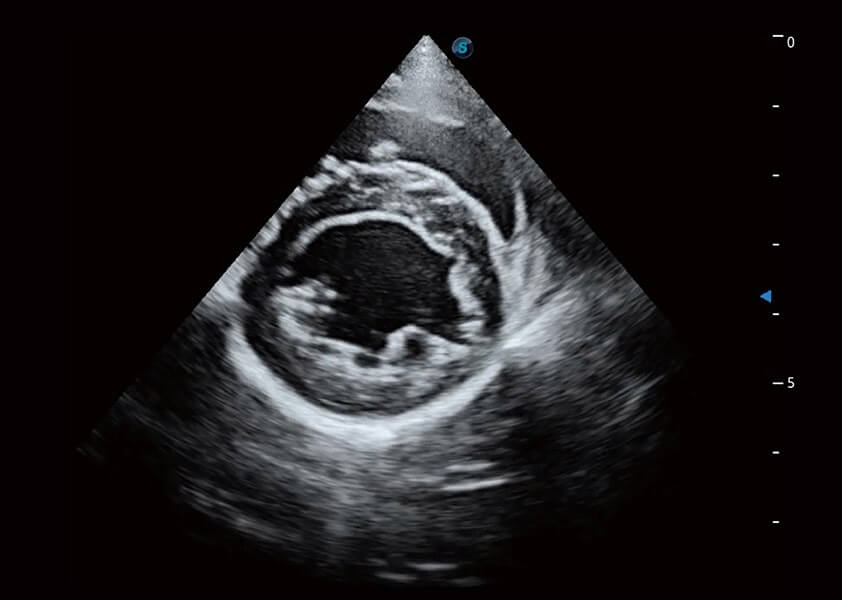

ProPet 60 作为一款高端台式动物超声设备,为动物医生的日常诊断提供了一系列贴合动物临床需求、解决临床实际问题的高级成像功能。凭借全系列高清探头,满足医生对腹部、心脏、生殖、浅表、肌骨等成像的所有需求,切实帮助您提升检查效率,提高诊断信心。

动物是人类最亲密的朋友和最值得信赖的伙伴。百老汇电子游戏官网也一直致力于探索动物专用的超声影像解决方案。 全新推出的ProPet系列,是百老汇电子游戏官网在动物超声影像智能化、专业化、精准化的一次跨越式革新。动物不能用言语来表述自己的不适,通过超声影像,ProPet系列搭建了动物医生与不同物种沟通的“桥梁”,为动物医生注入了“治愈之力”。